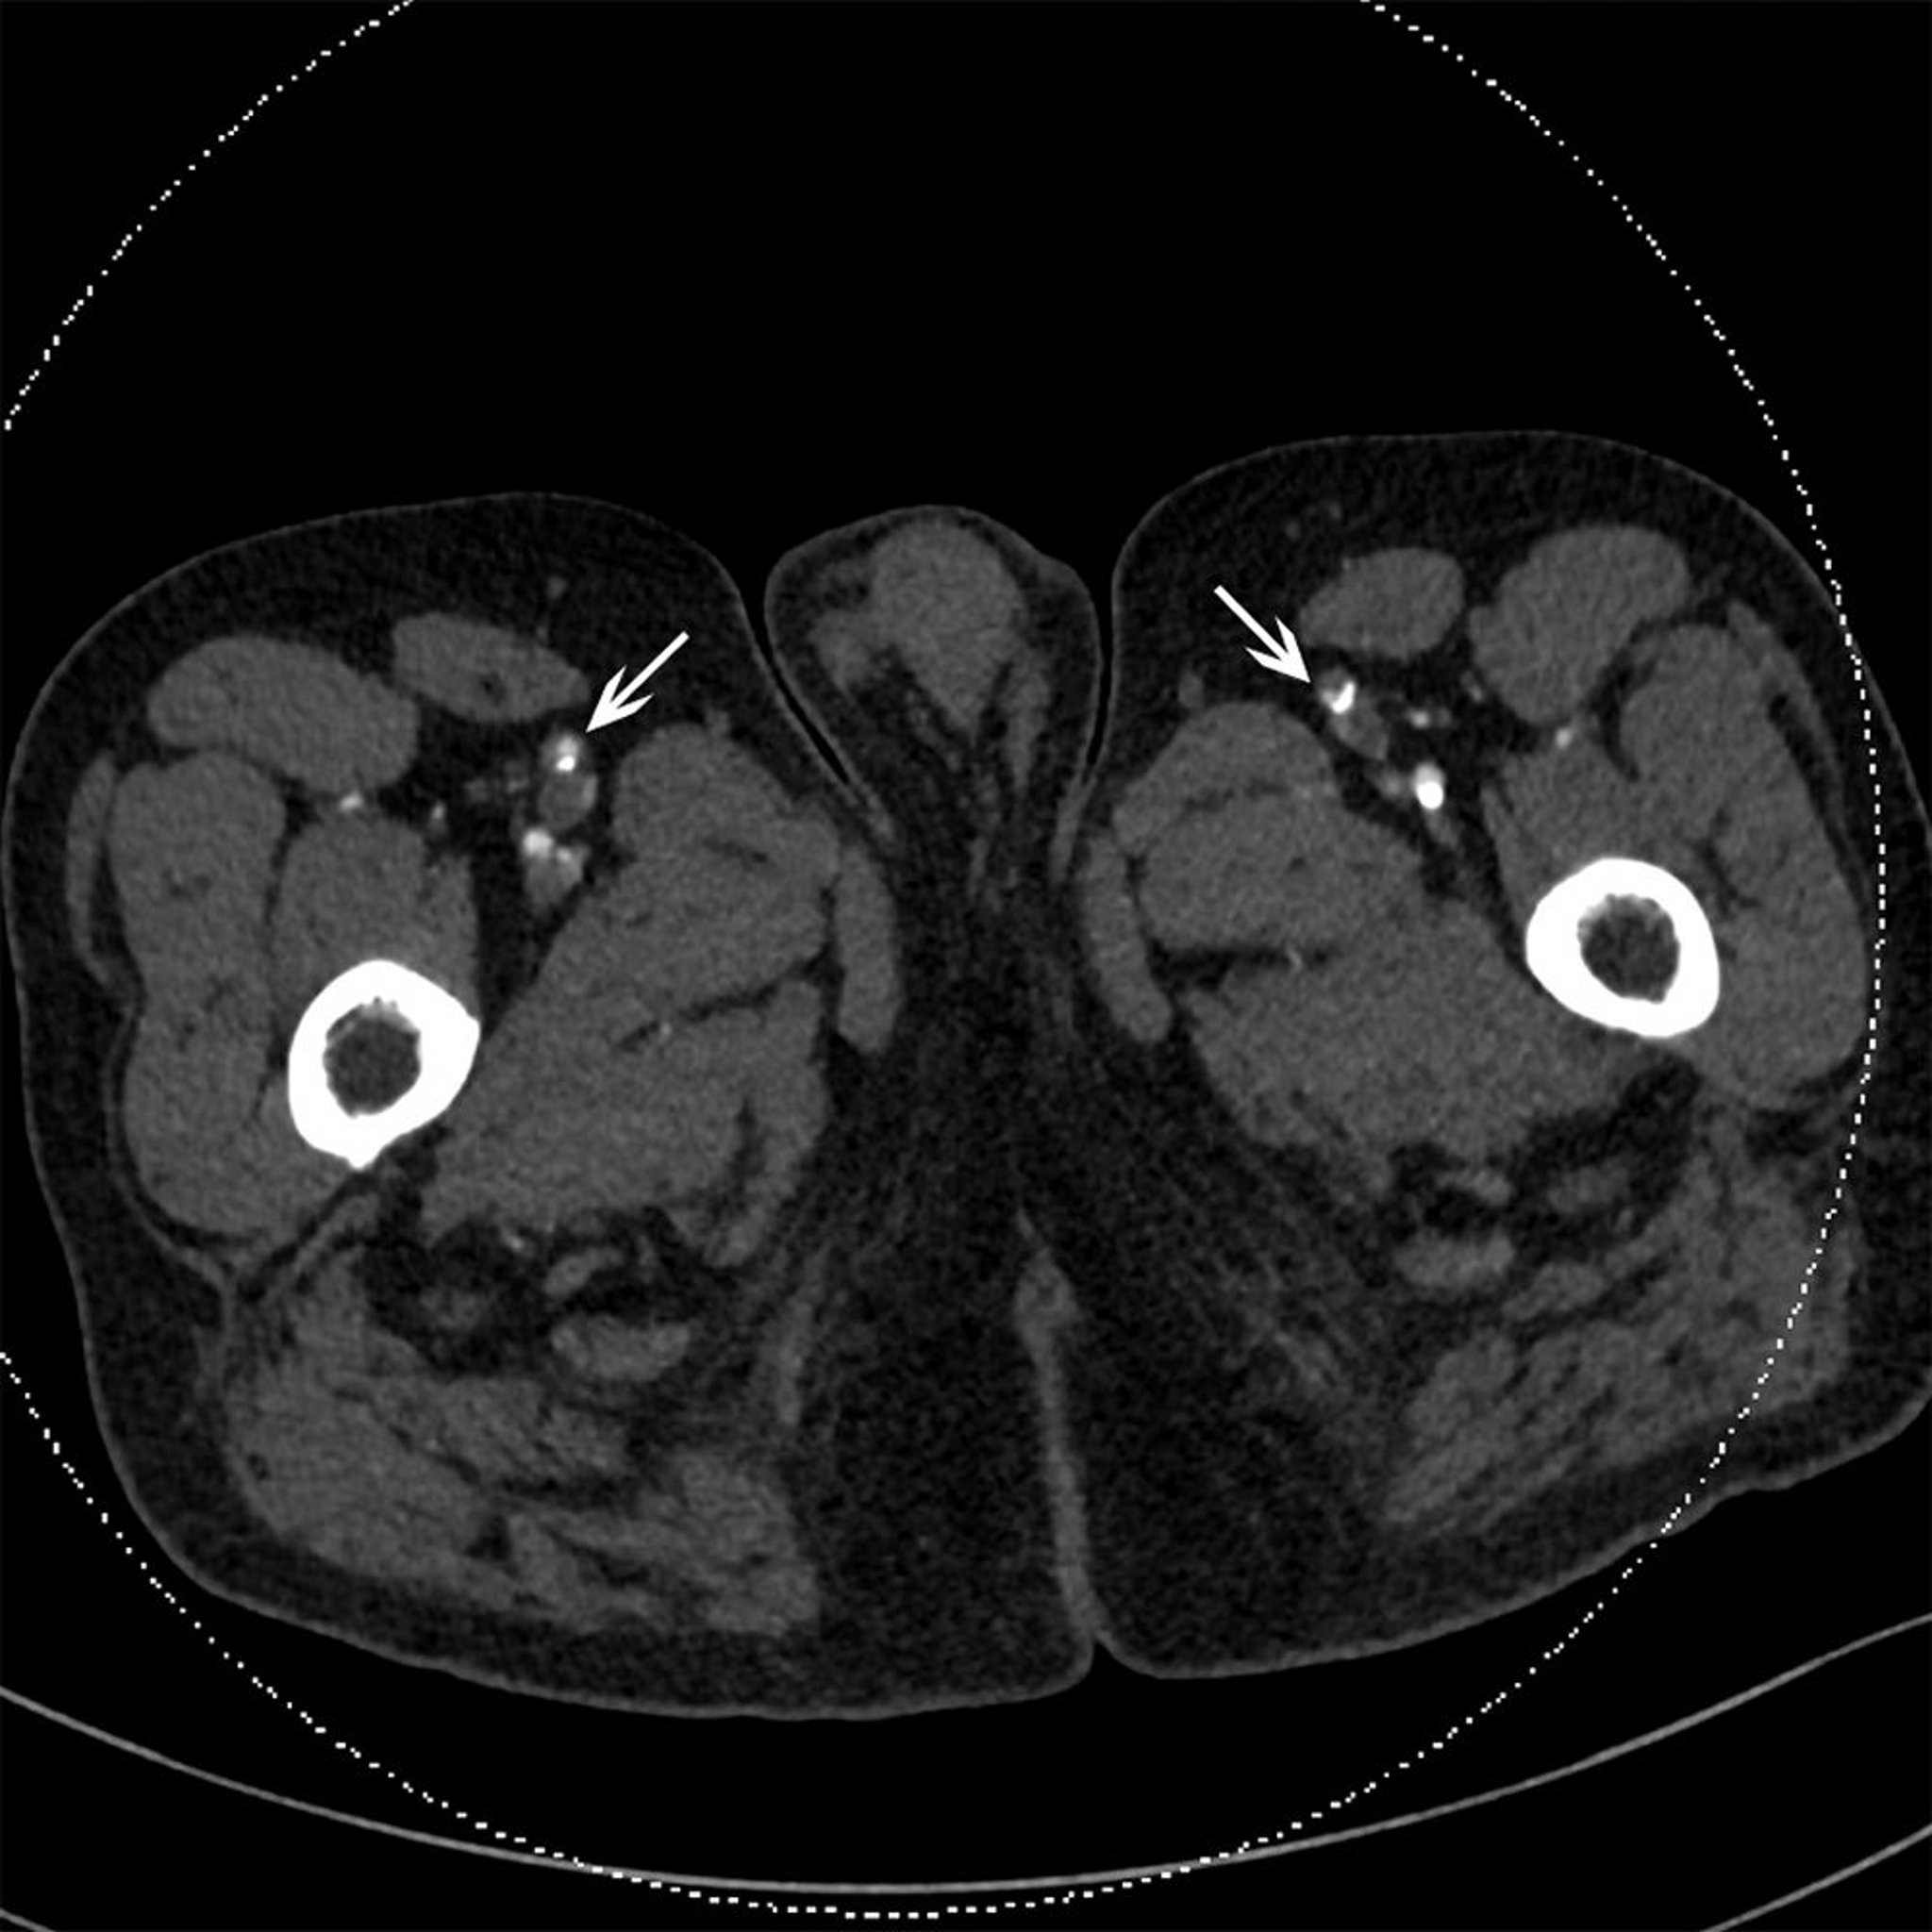

TDM d'un patient présentant une occlusion des artères fémorales superficielles

Cette TDM montre une plaque calcifiée bilatérale dans les artères fémorales superficielles (flèches).